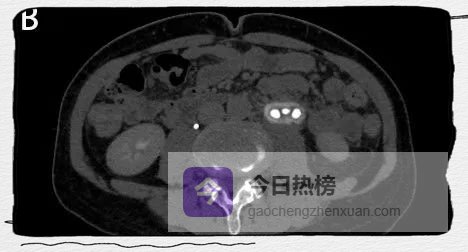

图4A

图4A-C

左侧肾盂及输尿管上段呈“双环及双腔样”改变,考虑夹层形成;三维重建可清楚的观察到撕裂肾盂及输尿管的真假腔并显示撕裂范围。